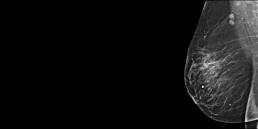

Femme de 75 ans, mammographie de depistage réalisé il y a un an normale.La patiente revient devant une tuméfaction du sein droit.

MammoScreen™ pointe une plage de surcroît de densité du QSE du sein droit.

L’échographie confirme une masse à l’union des quadrants externes du sein droit à contours irréguliers avec rigidité à l’étude élastographie.